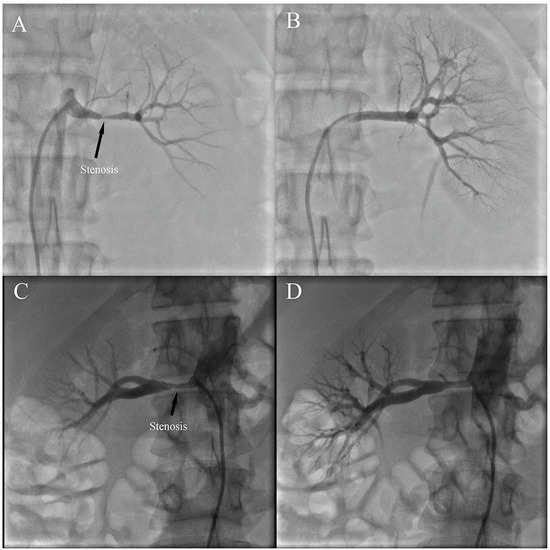

3.2. Angiographic Findings and Treatment